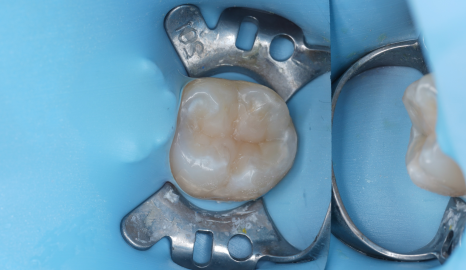

촬영일 : 250624

그래서 저는 오버레이 크라운을 선택했습니다.

오버레이는 치아 전체를 덮지 않고

기능적으로 약해진 부위만

정밀하게 수복하는 방식입니다.

삭제량을 줄이면서도 필요한 기능은

충분히 보완할 수 있는 방식이죠.

이 역시 러버댐을 설치한 상태에서

완전한 방습 하에 정밀 접착을 진행했습니다.

접착은 보철물 수명의 핵심이기 때문에

단순히 덮는 게 아니라 치아와 보철이

‘한 몸’이 되도록 세심하게 공들입니다.